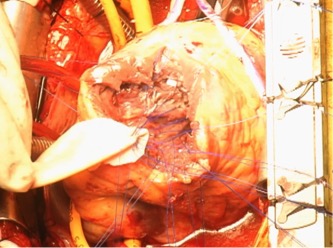

心室中隔穿孔に対するInfarct exclusion法の一部